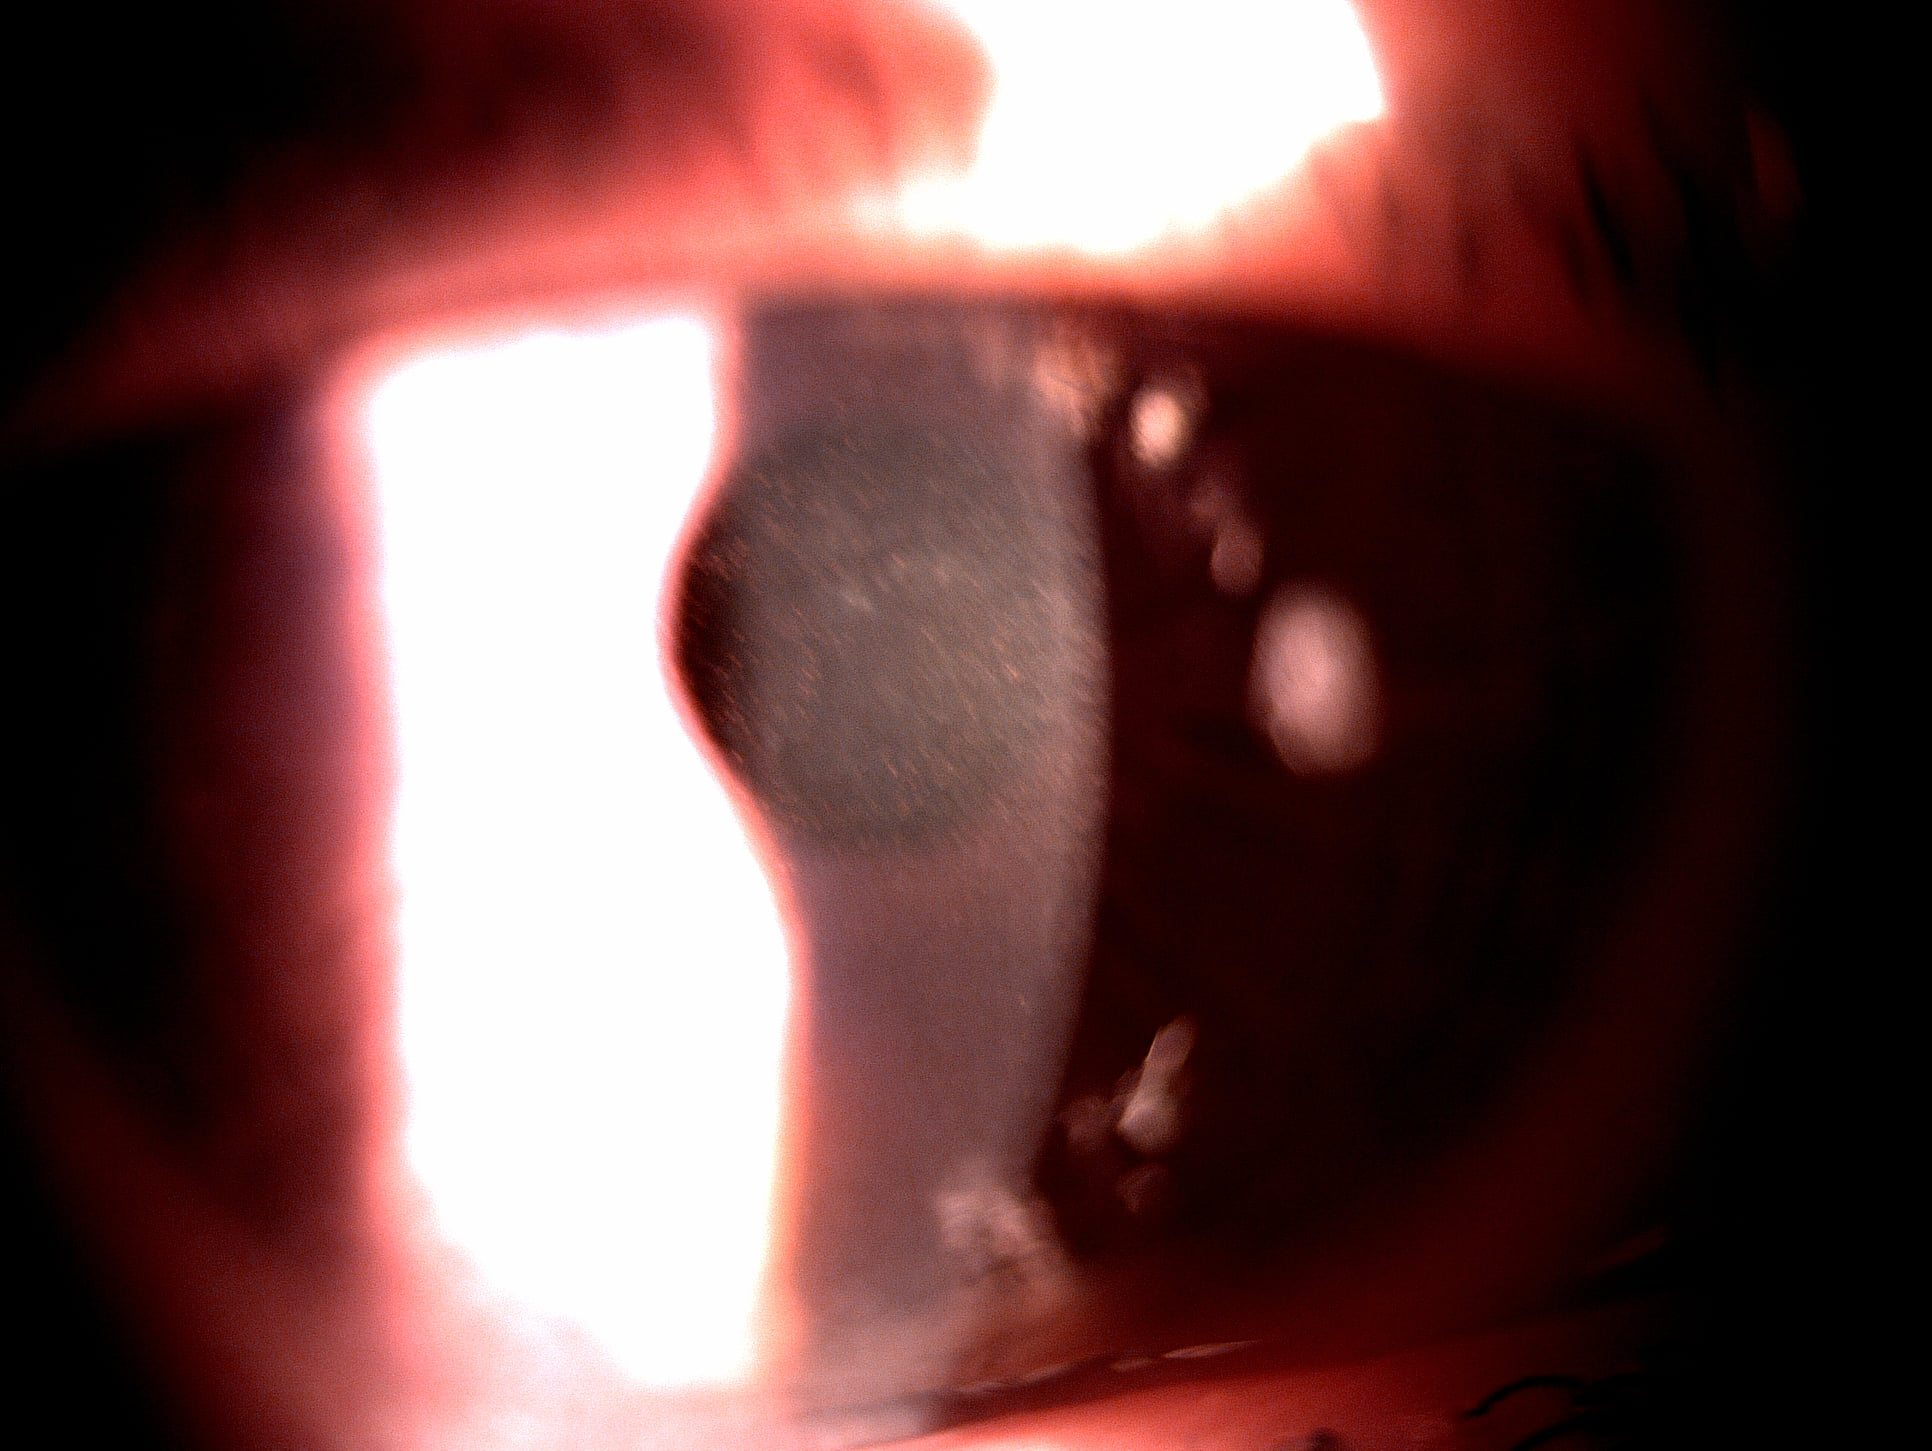

Mai jos, fotografii ale mai multor pacienti de-ai nostri cu Corneea Guttatta în faze medii, sau chiar avansate, la care am efectuat doar operația de cataractă, în urma căreia corneea a „supraviețuit” cu brio și nu a mai fost nevoie – cel puțin până acum – de un trasplant de cornee.